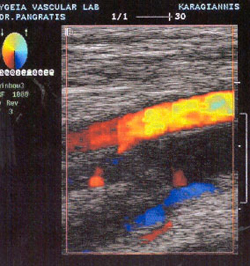

Η απεικόνιση έγχρωμης ροής αποτελεί το τελευταίο επίτευγμα στον κατάλογο των

τεχνικών μη αιματηρής διάγνωσης των αγγειακών παθήσεων. Η συσκευή έγχρωμης ροής

(TRIPLEX) χρησιμοποιεί probe γραμμικής δέσμης 7,5MHz για τα επιπολής αγγεία

ή 5MHz για τα εν τω βάθει αγγεία. Η αιματική ροή κωδικοποιείται ως έγχρωμη (κόκκινη

ή μπλε), αναλόγως της σχέσης της με τον προσανατολισμό της ηχητικής δέσμης.

Ο κορεσμός του χρώματος και για τις δύο κατευθύνσεις (αρτηριακή ή φλεβική ροή)

είναι ένδειξη της ταχύτητας. Σε χαμηλές ταχύτητες, το χρώμα που απεικονίζεται

είναι σκοτεινό κόκκινο ή μπλε και καθώς η ταχύτητα αυξάνει, το χρώμα γίνεται

προοδευτικά φωτεινότερο, ούτως ώστε να καταστεί σχεδόν άσπρο στις υψηλότερες

ταχύτητες. Τα πλεονεκτήματα της μεθόδου TRIPLEX, σε σχέση με την κλασική DUPLEX